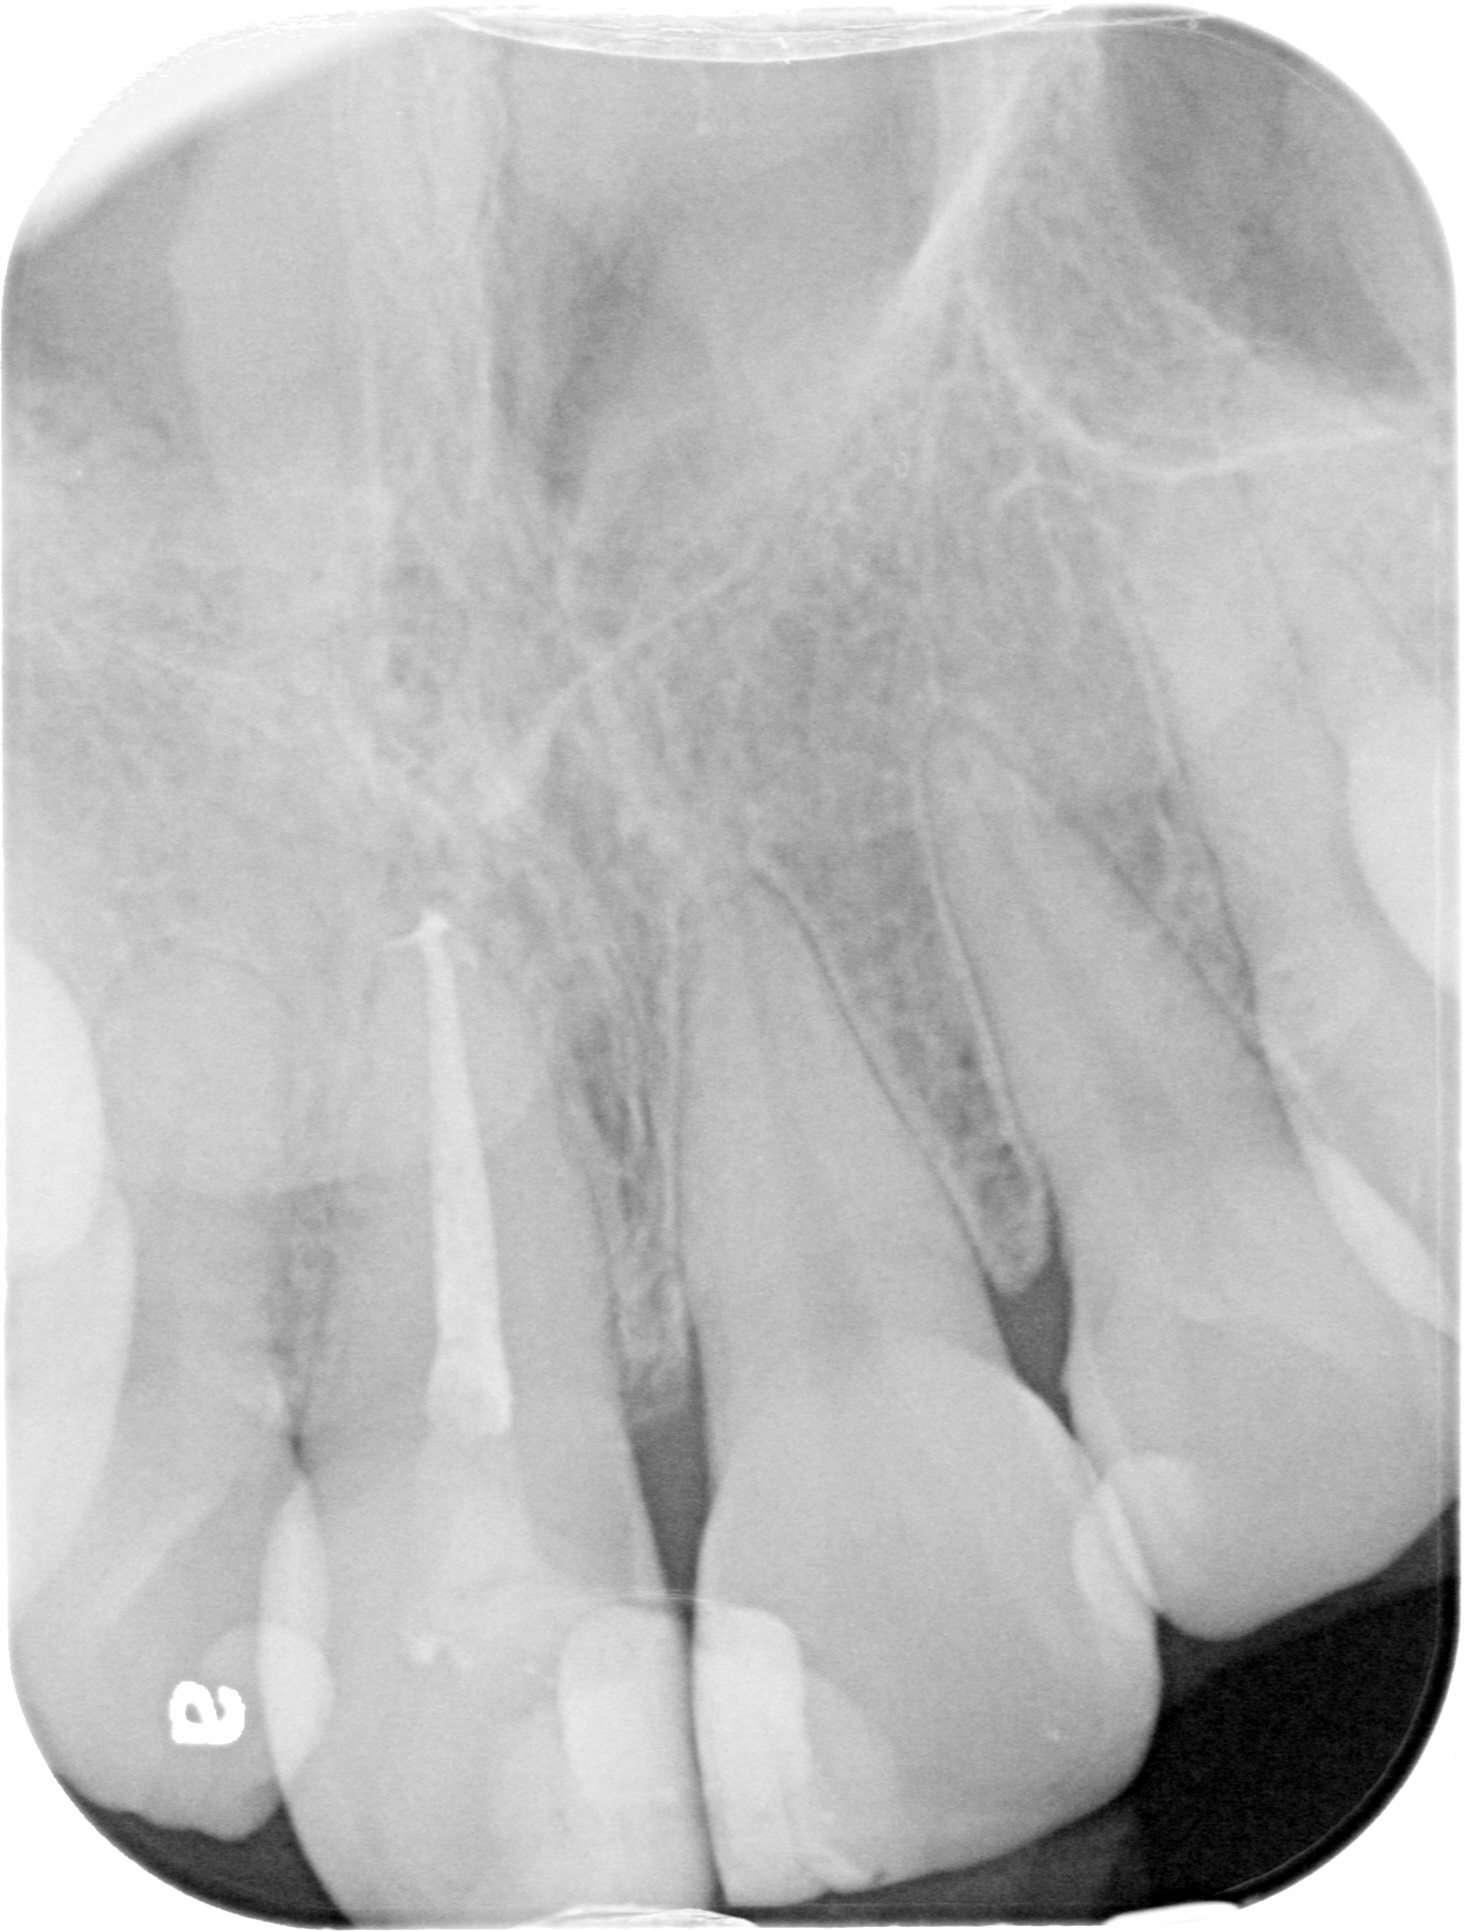

16 WITH PARTIALLY CALCIFIED CANALS

INITIAL

CANAL NEGOTIATION

WORKING LENGTH PATTENCY

FINAL